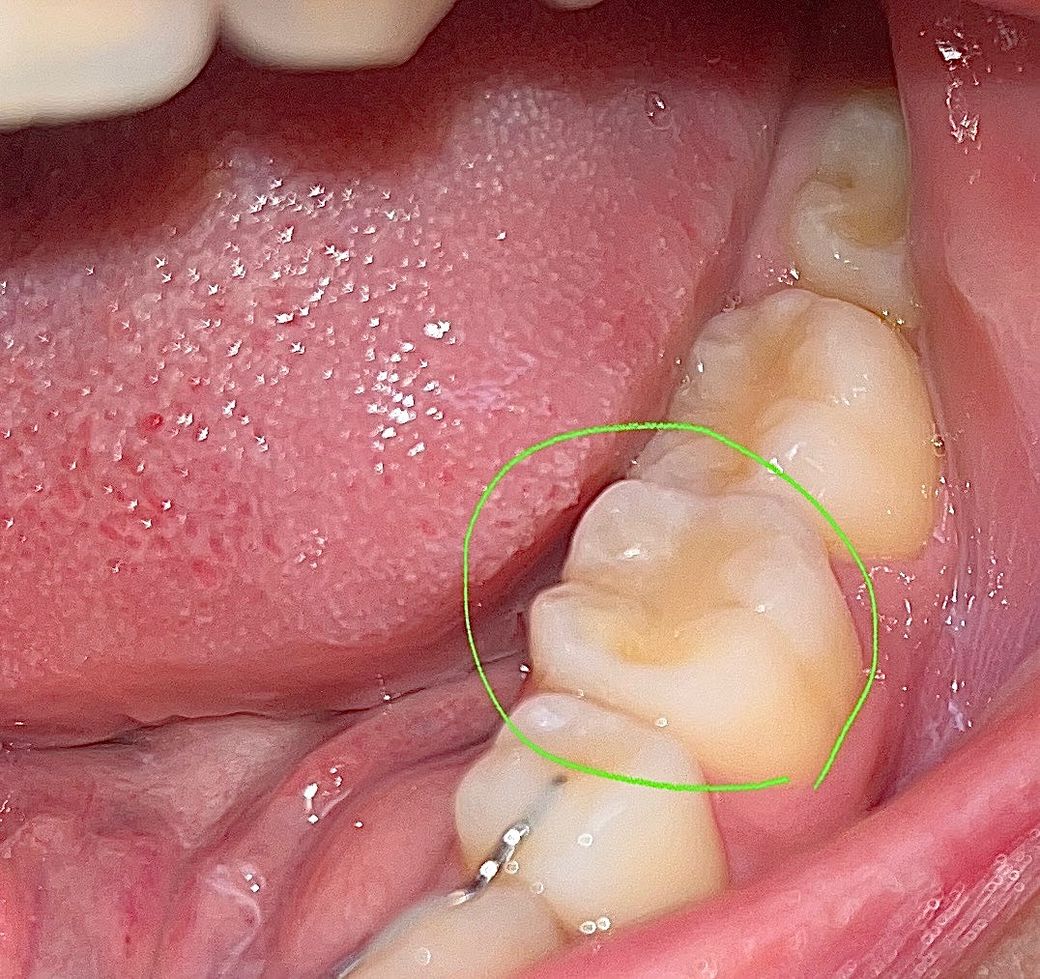

레진 치료 한지 2개월 정도 되었고 치료 전에는 전혀 통증이나 시림은 없었습니다. 치료 직후부터 지금까지 딱딱한 음식, 신 음식 먹을 때 찌릿하게 시립니다. 평소에는 양치할 때 아무 반응 없다가 신거 먹고 양치하면 특히나 시립니다 ㅠㅠ 찬물 뜨거운물에는 반응 없습니다.

사진에 레진 상태도 봐주세요.

사진으로 보였을 경우 레지는 잘 충전되어 있는 것으로 보입니다. 레진으로 충전한 부위가 불편감이 있거나 시린 느낌이 있다면 교합 간섭 등이 있을 수 있으며 레진의 접착이 잘 되지 않은 경우에도 해당 증상이 생길 수 있습니다.

사진상으론 레진이 별 문제없이 수복된 것으로 보이나 실제 검사는 해봐야압니다.